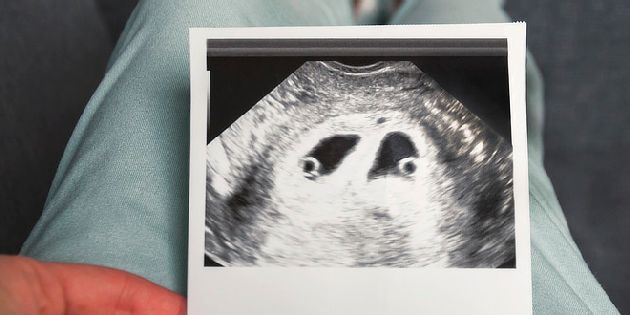

Oxytocinový zátěžový test hodnotí srdeční akci plodu během kontrakcí dělohy, aby lékař zjistil, jak dobře bude dítě zvládat porod. Za účelem vyvolání děložních kontrakcí je těhotné ženě podána malá dávka oxytocinu. Během testu je monitorována srdeční akce plodu.

Cílem oxytocinového zátěžového testu je zjistit, jaké jsou funkční rezervy plodu při uměle vyvolané zátěži (kontrakcích). Lze též posoudit připravenost mateřského organismu na porod – reaktivitu děložní svaloviny.

Při oxytocinovém zátěžovém testu se nejprve zajistí žilní přístup a aplikuje látka vyvolávající děložní kontrakce (stahy) za současného kardiotokografického sledování srdeční akce plodu, pohybů plodu a děložních kontrakcí. Celkově test trvá 60 minut. Prvních 20 minut je zaznamenávána klidová srdeční frekvence plodu, pohyby plodu a děložní kontrakce (non-stress test), poté je v průběhu dalších 20 minut aplikována nitrožilně infuze s oxytocinem za současného kardiotokografického sledování a posledních 20 minut probíhá znovu klidový kardiotokografický záznam. Poté je záznam vyhodnocen lékařem.